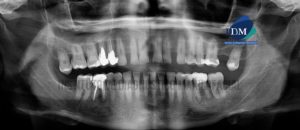

Paciente masculino de 64 años acude al Instituto de Diagnóstico Maxilofacial para la evaluación imagenológica de control. A la evaluación de la radiografía panorámica se